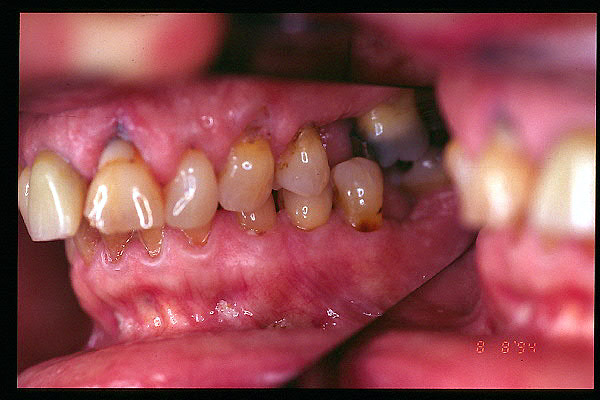

CM Desgaste por bruxismo, presencia de cálculo